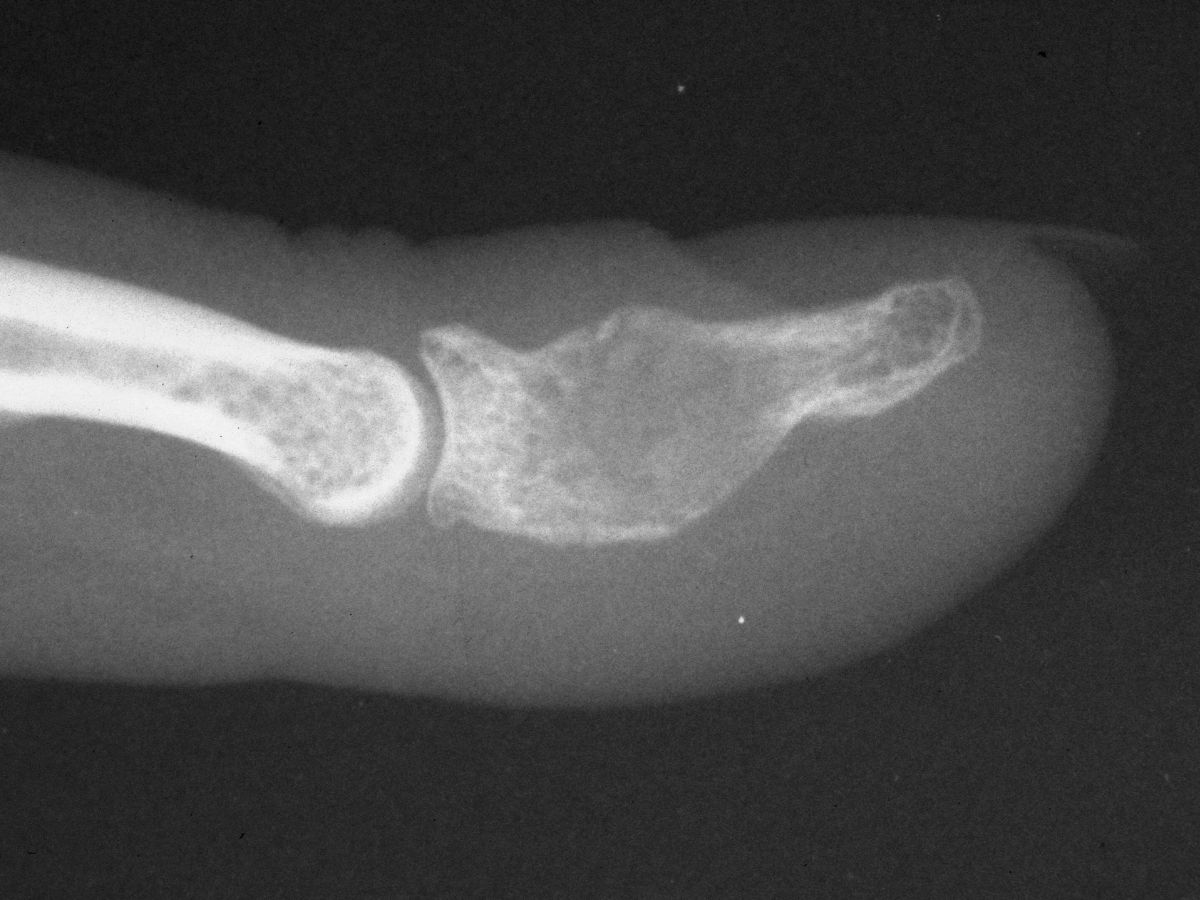

| Case 2. This patient presented months after having "injured" her middle fingertip, feeling that the finger was not normal. Xrays were consistent with an enchondroma and probable dorsal angulation from a healed pathologic fracture. |